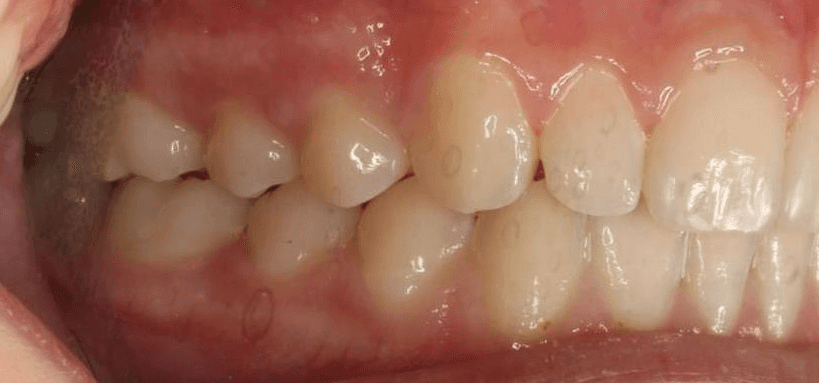

Final results

INTRAORAL